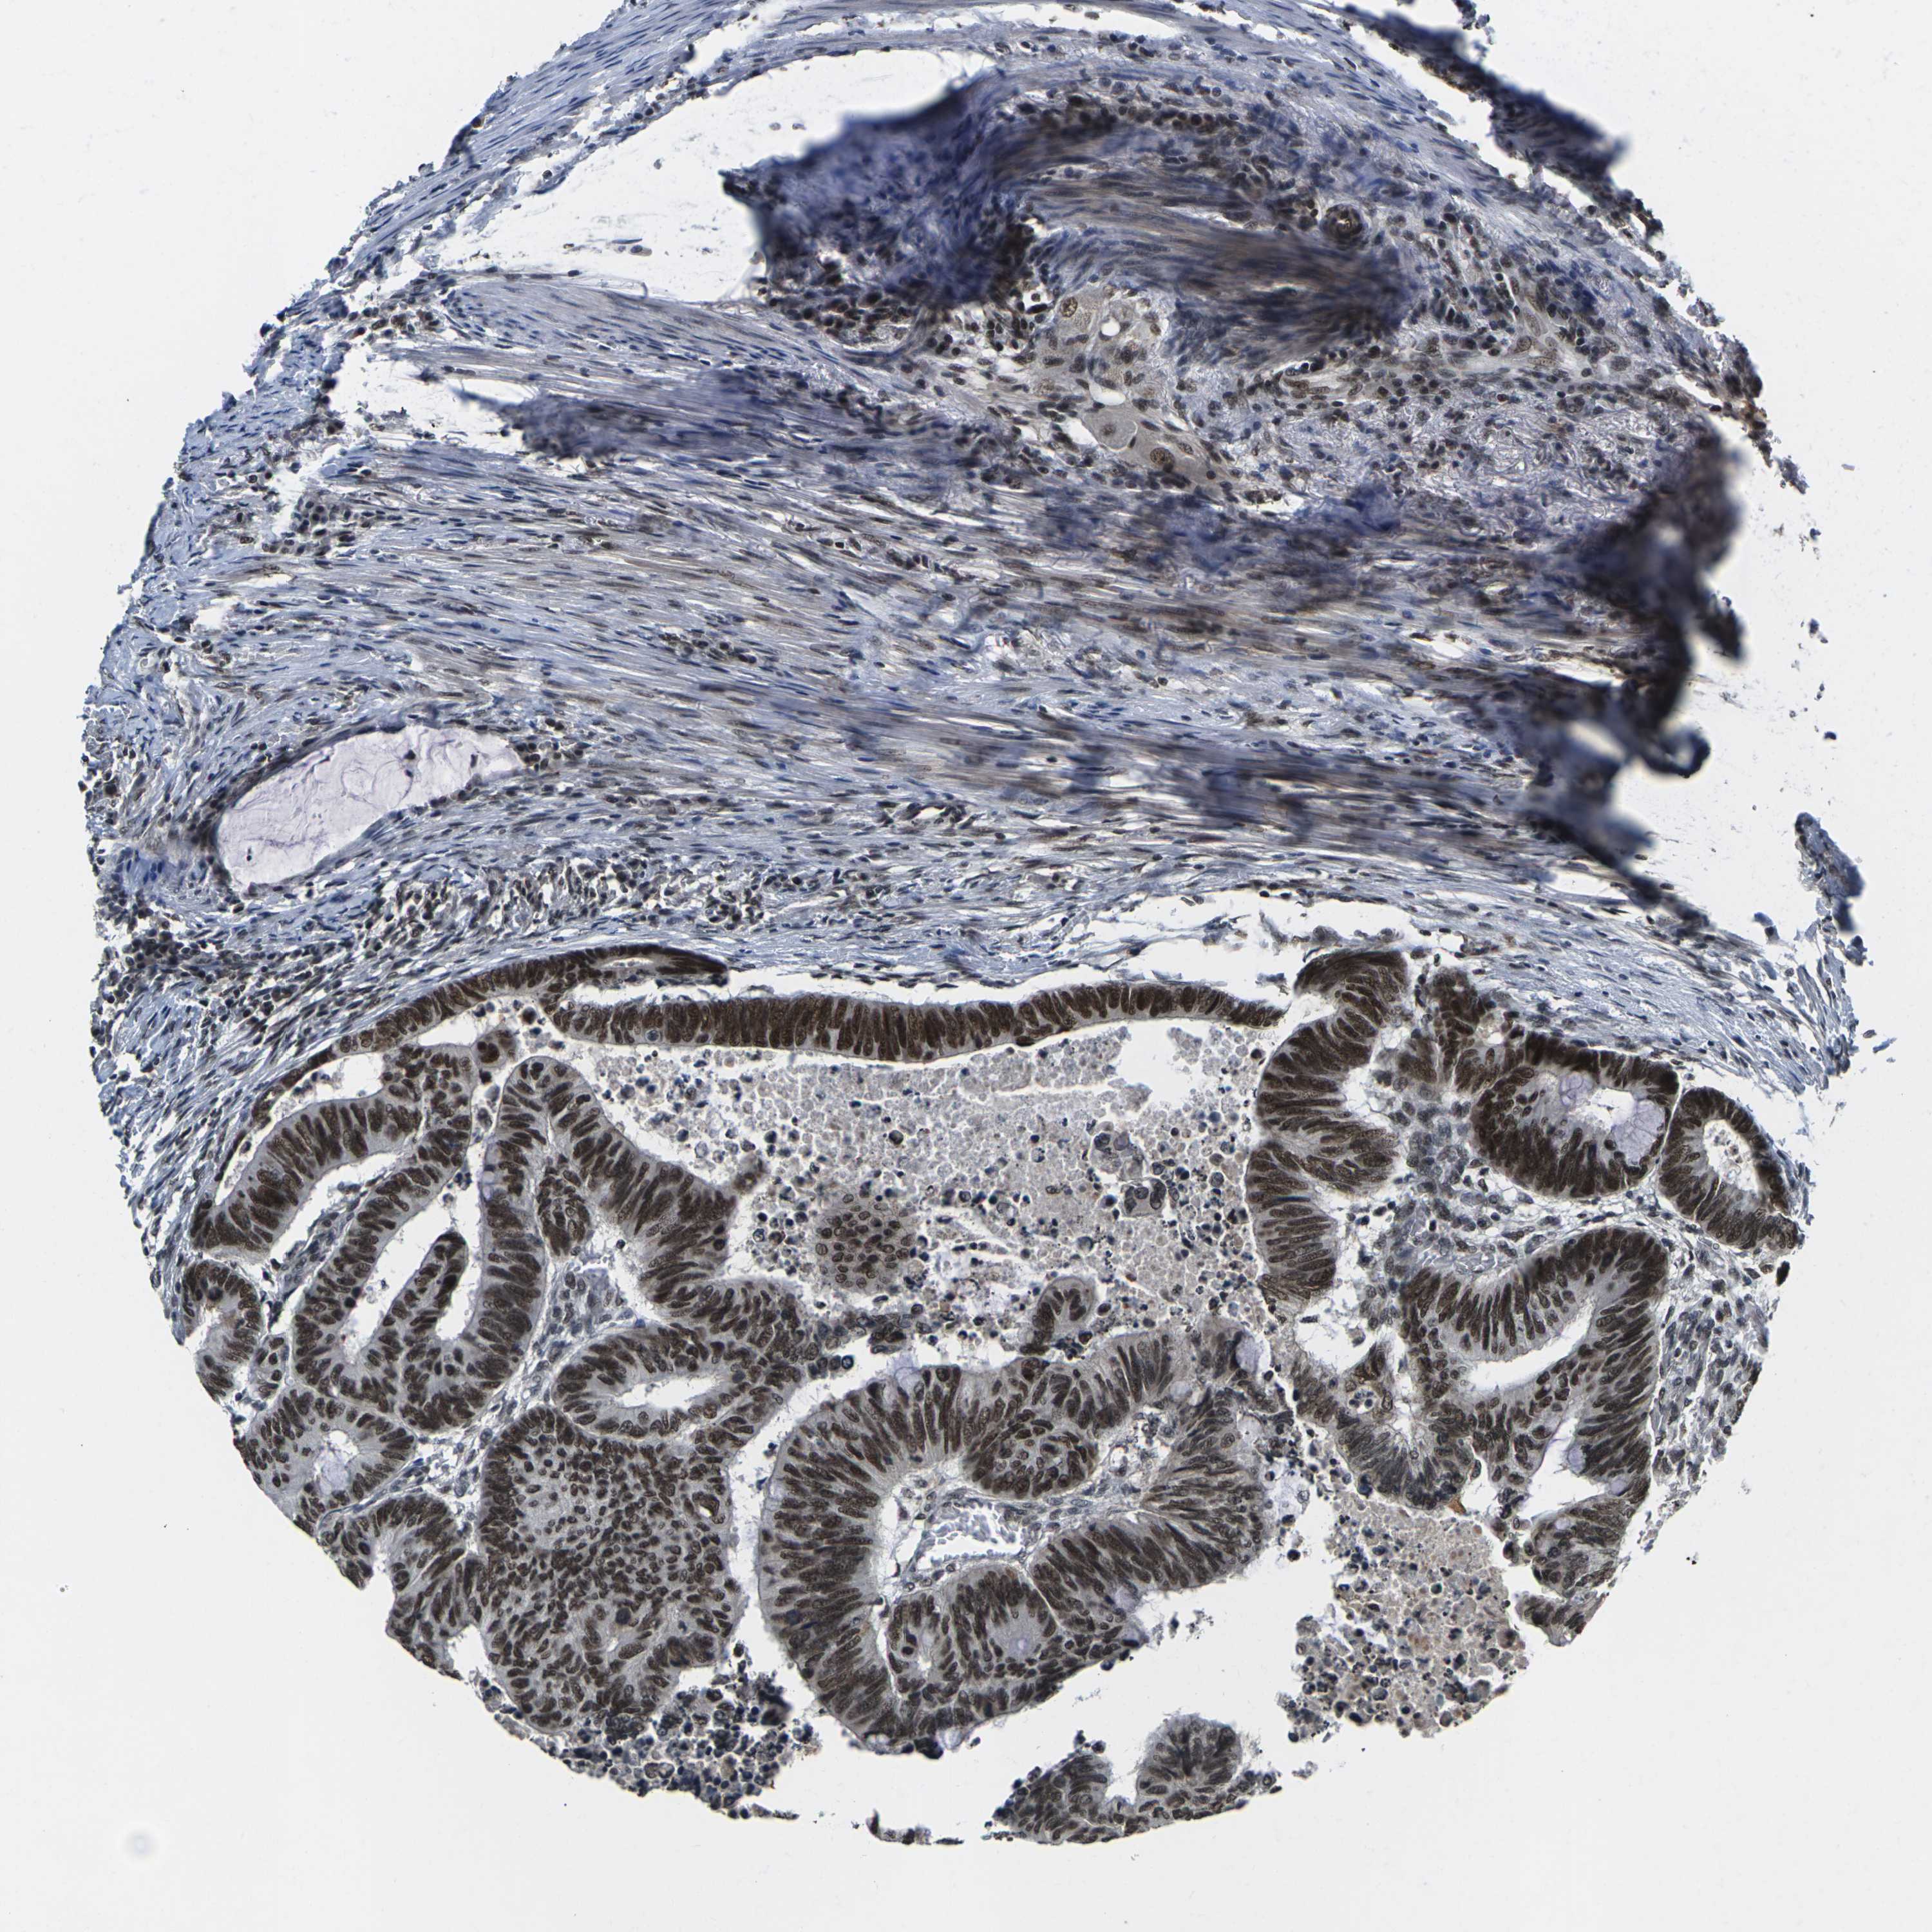

CANCER COLORECTAL CANCER Show tissue menu

Colorectal cancer

Human cancer

Colon adenocarcinoma